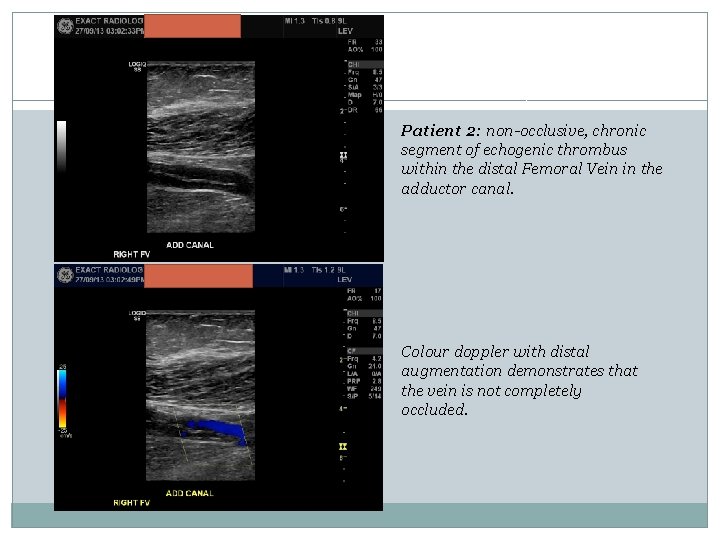

Patient 2: non-occlusive, chronic segment of echogenic thrombus within the distal Femoral Vein in the adductor canal. Colour doppler with distal augmentation demonstrates that the vein is not completely occluded.